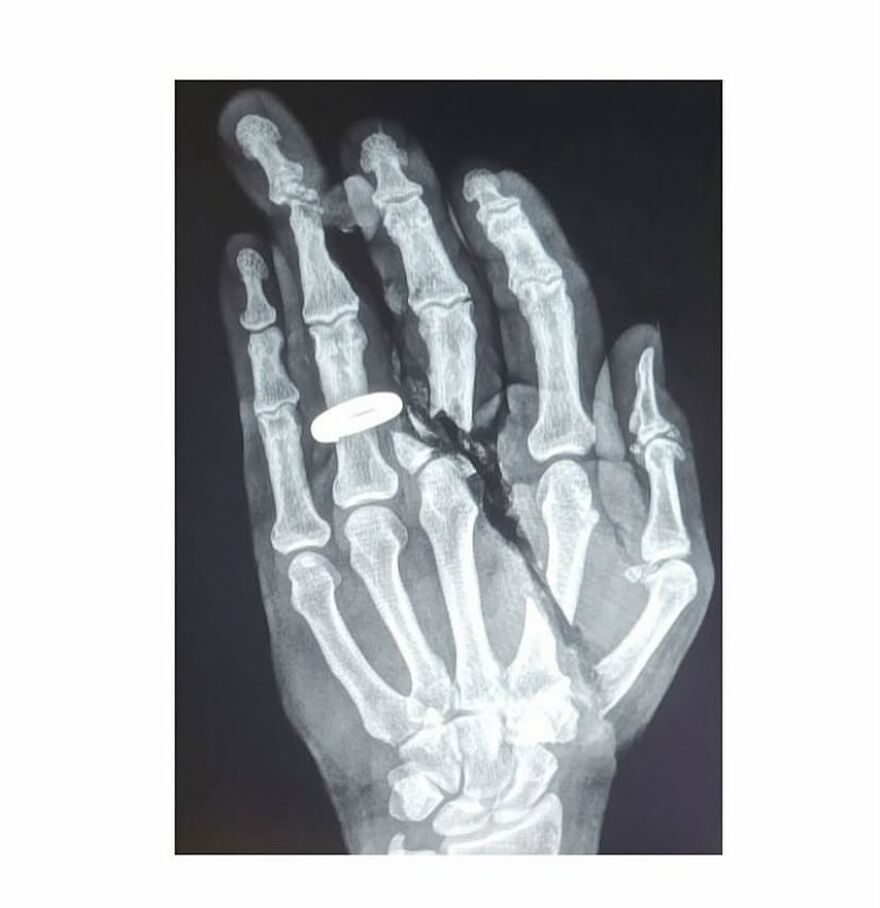

Plain radiograph of wrist joint shows polydactyly with duplication of ulna, duplication of ulnar side of carpal bones, metacarpals and phalanges, absence of radius and absence of thumb. Eight triphalangeal digits are seen. The middle phalanx of medial index finger is hypoplastic